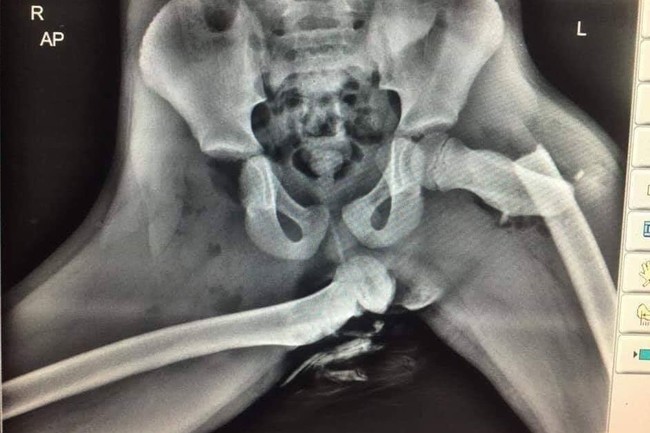

Hace unos días un agente de policía de Dyfed-Powys, en Gales, compartió en su Twitter una imagen que se ha hecho viral: una radiografía que muestra una pelvis totalmente destrozada. Según explicó el agente, Ian Price, la imagen pertenece al pasajero de un vehículo que viajaba en el asiento delantero con los pies apoyados en el salpicadero en el momento de la colisión.

La imagen pertenece a un servicio de ambulancias, y ha sido difundida, según explica el agente, con el objetivo de educar y prevenir daños a los demás: "Aquí hay una radiografía de horribles lesiones sufridas en un pasajero del asiento delantero que tenía los pies en el salpicadero en el momento de una colisión", reza el tweet.

Here is an X-ray of horrific injuries sustained to the front seat passenger who had their feet on the dashboard at the time of a collision. If you see your passenger doing it stop driving and show them this. pic.twitter.com/f3XCT8ePvi

Como se puede apreciar, el impacto debió ser tan fuerte que la articulación de la cadera derecha acaba rota y el fémur termina desgarrando la piel, posiblemente por efecto del airbag. La víctima no parece tener más de 9 o 10 años.